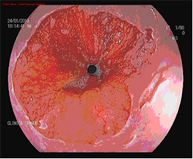

El diagnóstico se lleva a cabo mediante endoscopios de alta resolución con magnificación (aumento de la imagen), utilizando técnicas de cromoendoscopia añadidas, realizadas por endoscopistas especialistas en el diagnóstico precoz de lesiones precancerosas y la realización de biopsias que son analizadas.

Barrett 1Barrett 1 Barrett 2Barrett 2